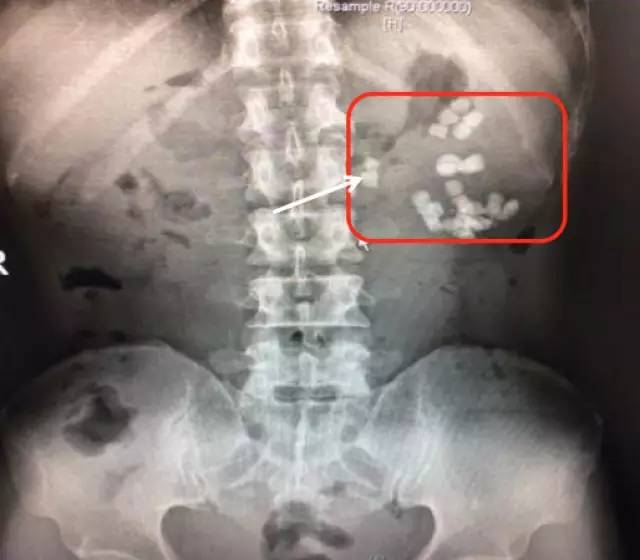

第一次来福建医科大学附属第一医院KUB检查结果

可见相当于左肾区(红框内)多发结节状密度增高影聚集,部分呈鹿角型

第二次来福建医科大学附属第一医院复查KUB检查结果

通过与4个月前的片子对比,我们可以看到虽然经过了两次手术,但是左肾区仍然遗留了大量而且分散的结石,甚至输尿管上段都有结石卡住(白色箭头所指结石),所以其症状仍然反复。

从他复查的这个KUB上,我们可以看到,左肾仍然有很多结石,而且还有结石掉到左侧输尿管上段引起了梗阻。这种结石如果不取干净,他肾脏里的结石就会时不时掉下来一颗两颗的,堵住输尿管,最终一定会把这个肾脏搞坏掉,我果断通知患者立马住院。